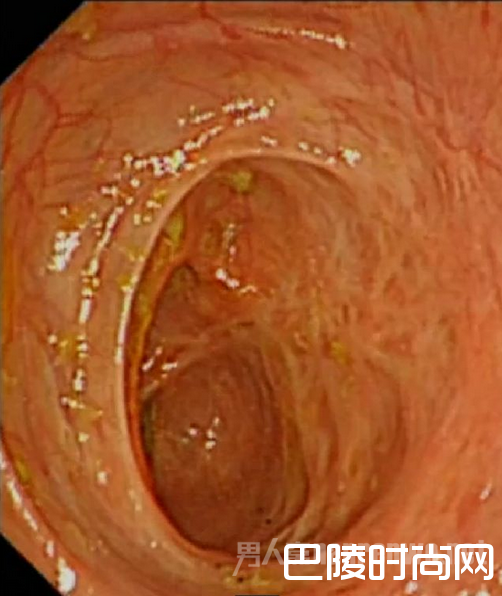

通过肠镜、CT 等检查发现,小王的整条肠子都有炎症,属于溃疡性结肠炎,除了左侧结肠堵塞外,右侧结肠也严重堵塞了,就连做肠镜的仪器都无法伸入。蒋益说,人的肠道正常直径一般为6 到7 厘米,有弹性,小王的肠道直径仅有1.5 公分左右,而且已堵塞到没有弹性,整根肠子几乎全“废”了。